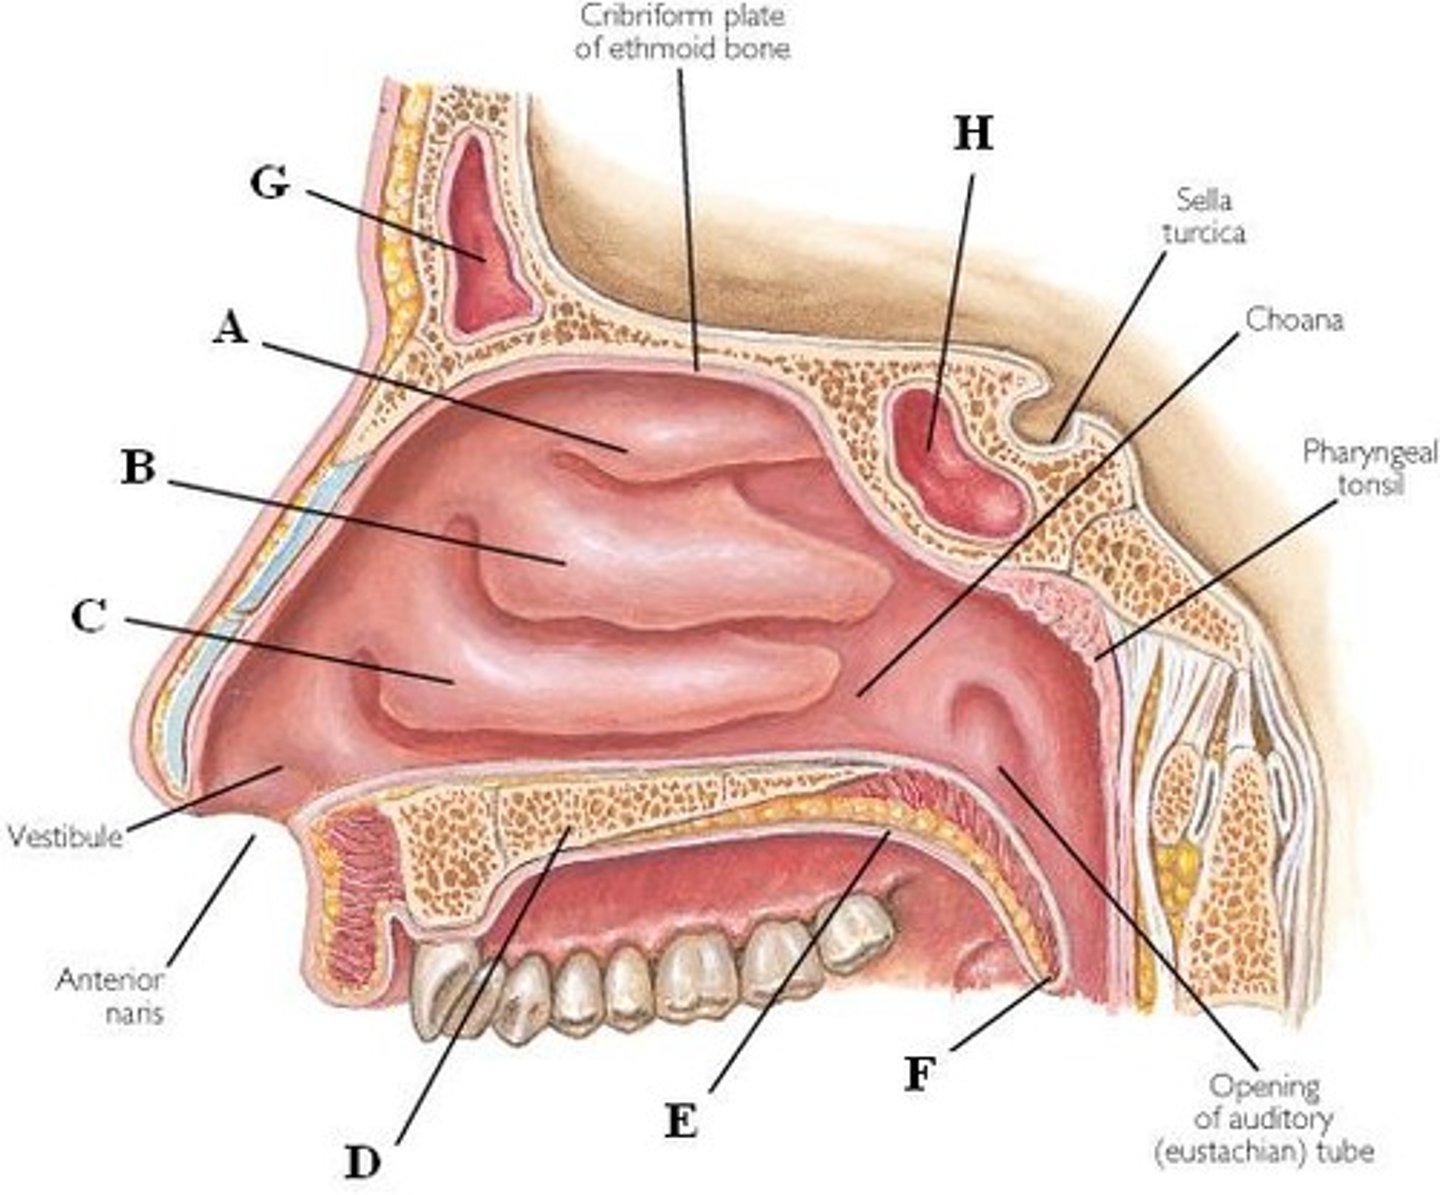

superior nasal conchae

Name A

middle nasal conchae

Name B

inferior nasal conchae

Name C